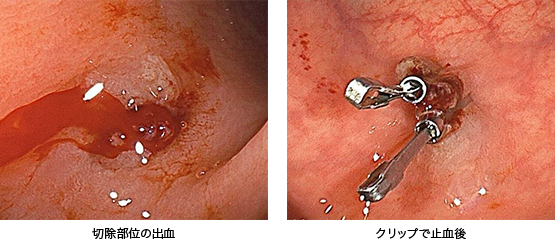

ポリープはスネアと呼ばれる内視鏡用の処置具で切除します(痛みなどを感じることは通常ありません)。傷口は出血することが多いため、クリップと呼ばれる器具で縫合します。